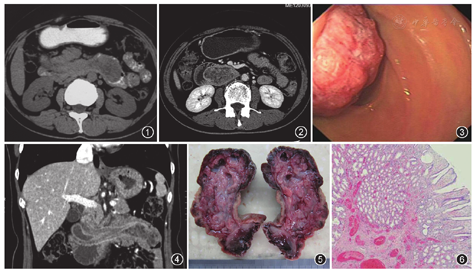

女,49岁。因间断腹痛、黑便1年余,加重8 d入院。体检:贫血貌,腹软,右上腹压痛、无反跳痛及肌紧张。实验室检查:红细胞2.7×1012/L(正常参考值:3.5×1012~5.0×1012/L),血红蛋白76 g/L(正常参考值110~150 g/L),消化道肿瘤标志物均未见异常。入院前1个月腹部CT平扫示空肠近段腔内软组织肿块,其内密度欠均匀,十二指肠降段与水平段结构紊乱(图1)。入院后行腹部增强CT示十二指肠降段与水平段交界区内见腔内不均匀强化高密度影,部分边界不清,大小为2.5 cm×2.4 cm(图2);近段空肠腔内未见病变,诊断为十二指肠降段肿物并十二指肠空肠套叠。因患者症状持续,3 d后复查胃镜及腹部增强CT,胃镜示十二指肠降段内见一巨大肿物,大小为7.0 cm×3.0 cm,有一粗蒂,其基底部位于降部入口,肿物头端粗糙,触之易出血,近基底部分肿物表面光滑(图3);增强CT扫描见近段空肠一轻度强化的团块状软组织密度影,十二指肠降段部分及水平段向远侧小肠内套入,局部呈4层肠壁结构,肿物头侧并见多个囊状低密度影(图4)。综合多次CT与胃镜检查结果,诊断为十二指肠降段肿瘤并复发性肠套叠。

行剖腹探查术,术中十二指肠降部可触及一个带蒂圆形肿物,蒂长约6.0 cm,直径约5.0 cm。于肿物蒂部切开肠管并还纳套叠远侧部,于蒂部切除肿物。肿物大小6.0 cm×2.5 cm×2.4 cm,剖面呈灰白色、质软,并散在分布多个囊腔,其内富含黏液(图5)。显微镜下见肿物主要由分化成熟的Brunner腺体构成,其间伴有导管和散在的纤维间隔及平滑肌成分,亦有少量淋巴细胞及浆细胞浸润,其表层覆盖的十二指肠黏膜上皮未见异型增生(图6)。术后病理诊断为Brunner腺瘤。患者术后症状缓解,恢复良好出院。

钡餐上消化道造影及十二指肠低张造影诊断本病无特异性。CT和MRI对直径≥1 cm的病灶易检出,虽不能定性,但CT显示肿瘤引起的肠套叠具有优势,CT增强扫描可以清晰显示肠套叠的4层肠壁结构。本例腹部CT平扫及增强扫描显示肿瘤密度不均匀,且呈不均匀强化,与肿瘤组织内含有平滑肌、纤维组织、导管以及炎性细胞等多种组织细胞成分有关。十二指肠固定于后腹膜致移动性小,故十二指肠肠套叠罕见。从多次CT检查与内镜结果可以看到患者历经肠套叠、自发缓解及再次复发套叠的反复演变,可能与该肿瘤蒂较长、体积大有关。本病常需与十二指肠内其他肿瘤(如脂肪瘤、间质瘤、神经源性肿瘤等)相鉴别。